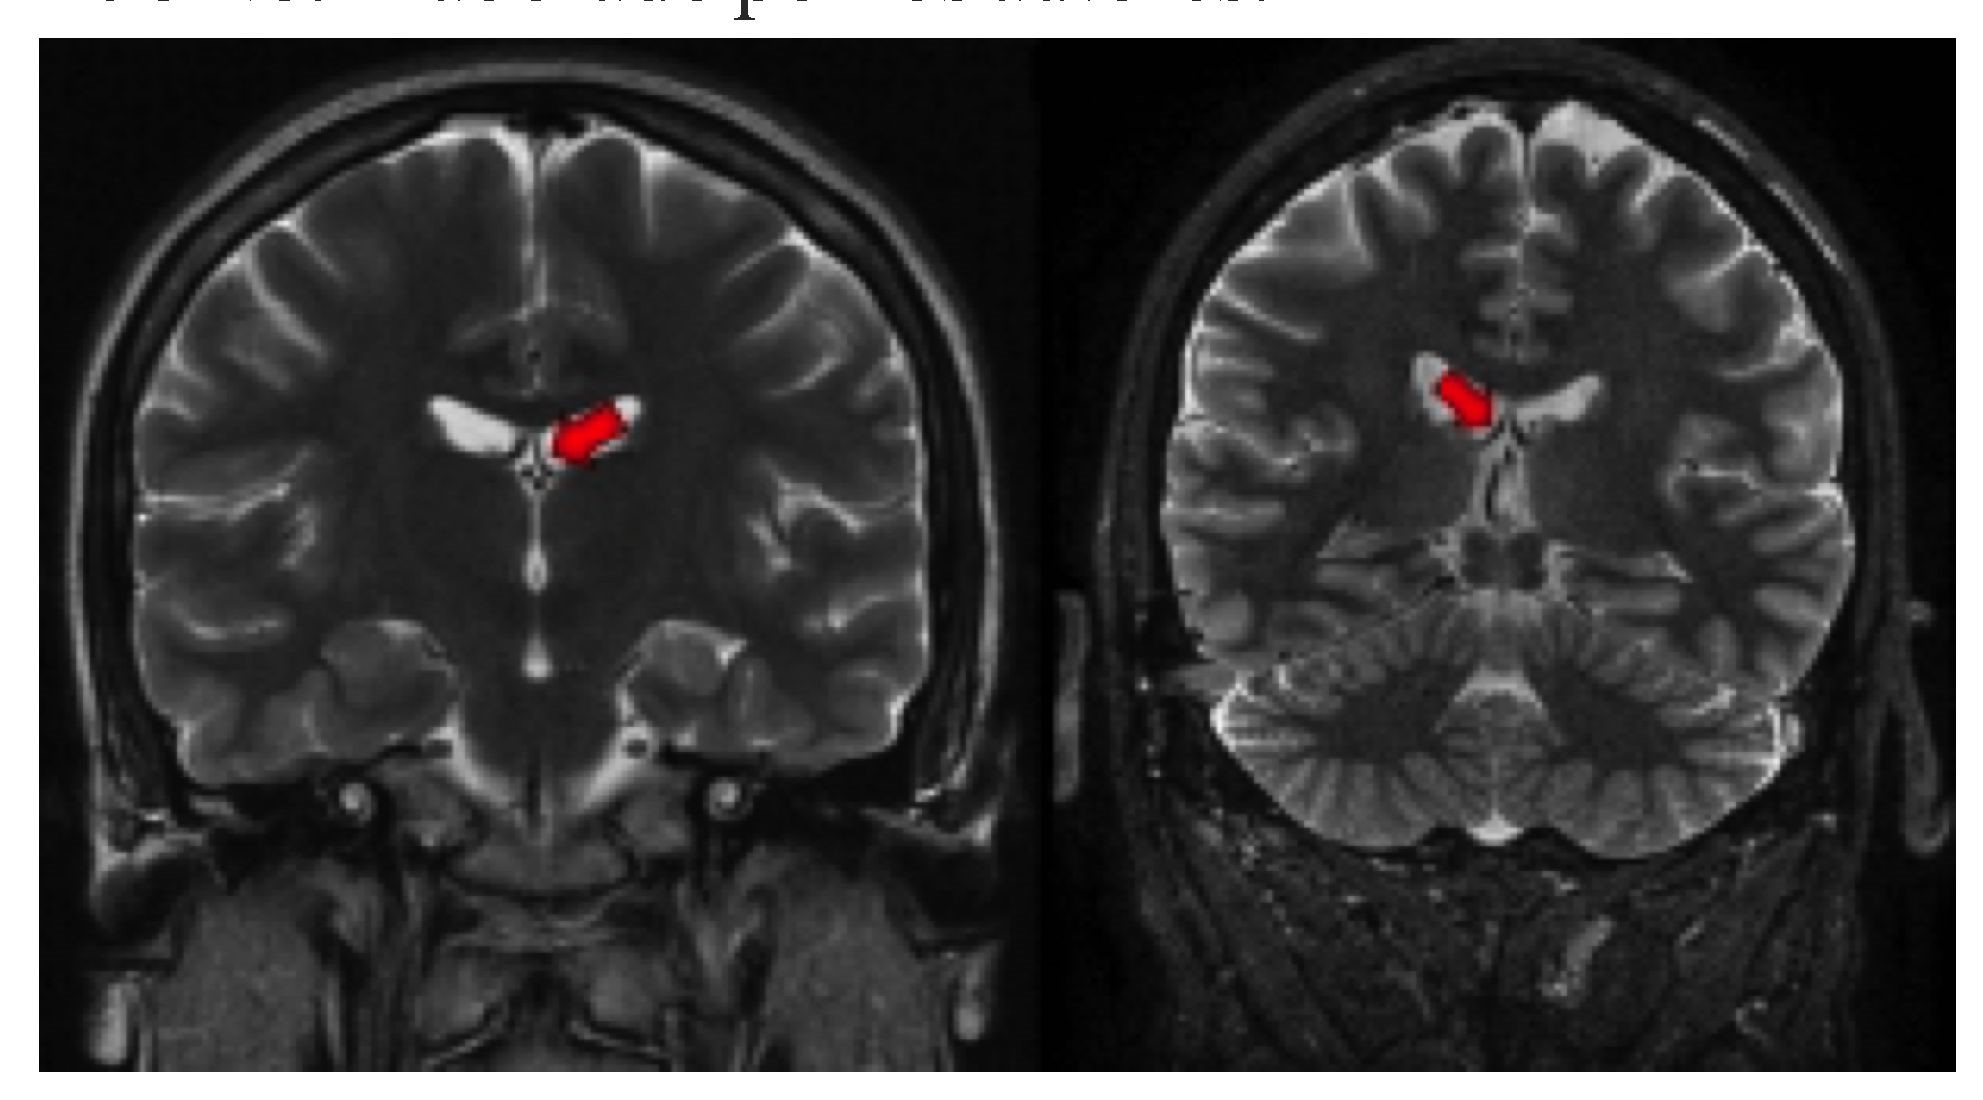

Los signos secundarios incluyen pérdida de la arquitectura interna del hipocampo, pérdida de las digitaciones de la cabeza del hipocampo que normalmente contiene dos o tres digitaciones (Figura 3izquierda), dilatación del asta temporal ipsilateral asociada a la atrofia hipocampal, aumento de la intensidad de señal de la amígdala, pérdida de volumen del lóbulo temporal (31), atrofia del cuerpo mamilar (Figura 3derecha), atrofia del fórnix(Figura 4), atrofia del tálamo y atrofia del giro del cíngulo, ipsilateral a la afectación hipocampal (32-34).

La tractografía puede demostrar reorganización estructural de los tractos asociados a memoria y lenguaje de acuerdo con la localización de la lesión y a la dominancia hemisférica; en pacientes con dominancia hemisférica izquierda y esclerosis temporal mesial ipsilateral se ha demostrado aumento de los tractos de sustancia blanca del hemisferio contralateral como resultado de reorganización funcional del lenguaje en regiones corticales contralaterales (61,62). La evaluación del fascículo arcuato que conecta las áreas receptivas y productivas del lenguaje ha demostrado ser mayor en el hemisferio dominante y esa asimetría se reduce cuando existe lesión en el hemisferio dominante secundaria a reorganización funcional (63,64), mientras que la evaluación del fascículo uncinado (Figura 7) y los datos de reorganización neuronal permiten predecir el desarrollo de afasia (65).